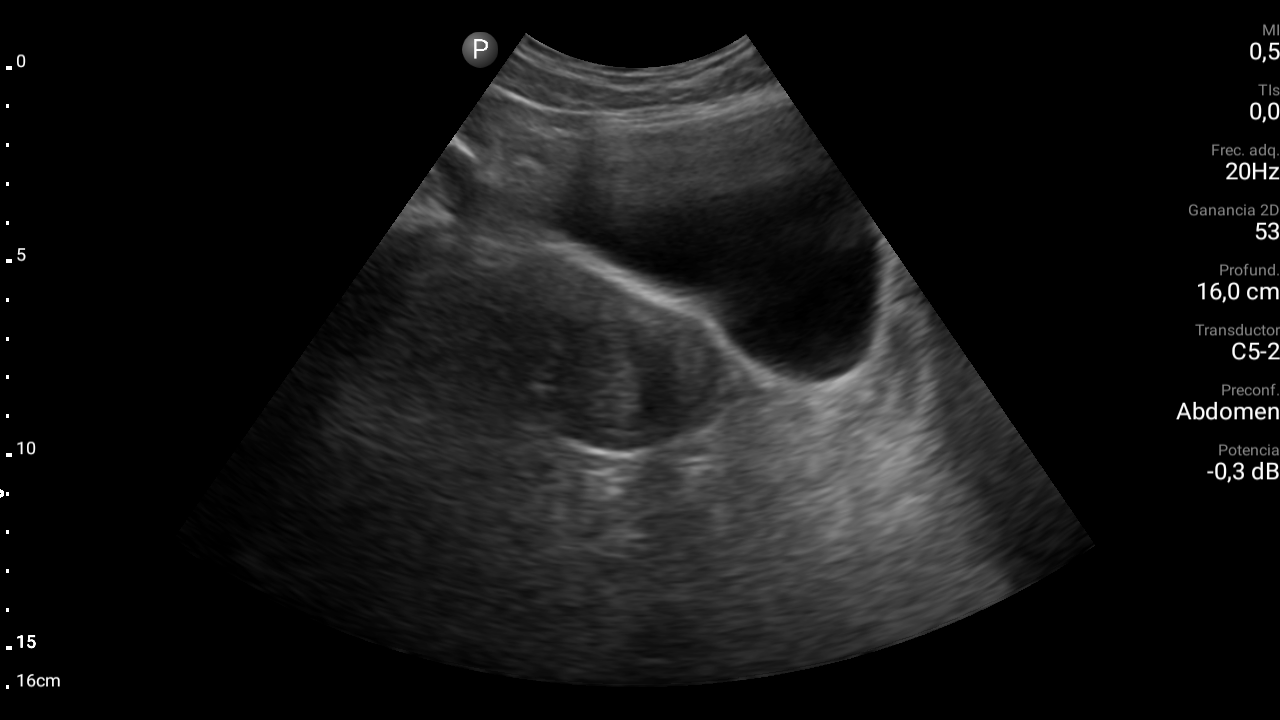

En ecografía abdominal se observa masa hipoecoica dependiente de útero por lo que se remite de forma preferente a ginecología.

En ginecología le realizan ecografía transvaginal, siendo diagnosticada de mioma uterino.